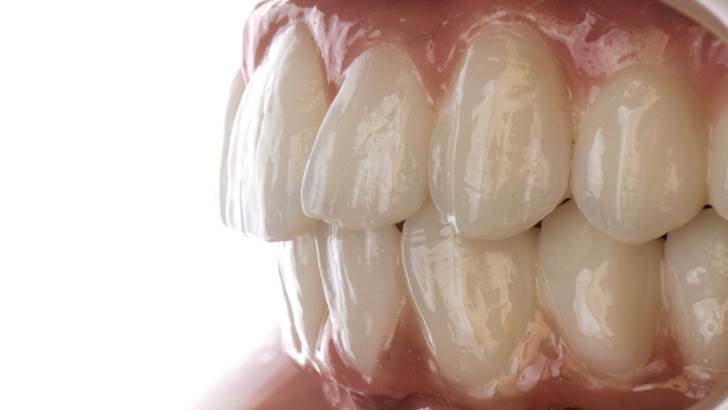

“AnyRidge shows excellent esthetic results

with Zirconia prosthesis in full-mouth rehabilitation case . ”

Clinical case: AFull transition from natural teeth to all-on-6 bridges

with AnyRidge implants